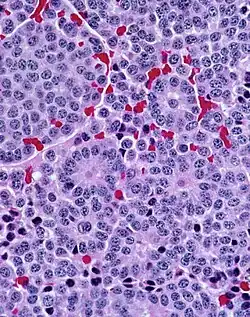

A carcinoid (also carcinoid tumor) is a slow-growing[1] type of neuroendocrine tumor originating in the cells of the neuroendocrine system. In some cases, metastasis may occur. Carcinoid tumors of the midgut (jejunum, ileum, appendix, and cecum) are associated with carcinoid syndrome.

Carcinoid tumors are the most common malignant tumor of the appendix, but they are most commonly associated with the small intestine, and they can also be found in the rectum and stomach. They are known to grow in the liver, but this finding is usually a manifestation of metastatic disease from a primary carcinoid occurring elsewhere in the body. They have a very slow growth rate compared to most malignant tumors. The median age at diagnosis for all patients with neuroendocrine tumors is 63 years.

Carcinoid tumors are apudomas that arise from the enterochromaffin cells throughout the gut. Over two-thirds of carcinoid tumors are found in the gastrointestinal tract.[7]